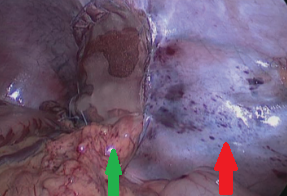

Red arrows — Anterior and posterior cystic arteries. Green arrow — Cystic duct (Courtesy Dr. V. Penopoulos)